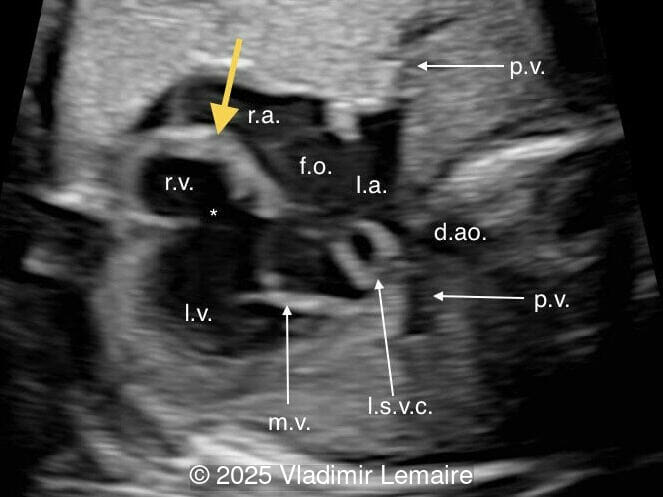

We present a case of isolated tricuspid atresia type 1 with persistent left superior vena cava. No other extracardiac anomalies were found. Our diagnosis was confirmed after birth.

In the images below, the abbreviations are as follows: RA: right atrium; RV: right ventricle; LV: left ventricle; MV: mitral valve; LA: left atrium; FO: foramen ovale; SVC: superior vena cava; LSVC: left superior vena cava; PV: pulmonary veins; PA: pulmonary artery; MPA: main pulmonary artery; RPA: right pulmonary artery; AO: aorta; dAO: descending aorta; aAO: ascending aorta; DA: ductus arteriosus; T: trachea; * marks the ventricular septal defect.

Tricuspid atresia is a rare anomaly, with an incidence of 0.08 per 1,000 live births, and is characterized by the lack of communication between the right atrium and ventricle. As a result, the right ventricle is hypoplastic. The tricuspid valve apparatus does not develop in the majority of cases, and the right atrioventricular junction appears as echogenic thickened tissue on ultrasound examination. An inlet type ventricular septal defect is always present, and the size of the right ventricle depends on the size of the ventricular septal defect. As a consequence of the obstructed tricuspid valve, a large interatrial communication, in the form of a widely patent foramen ovale or atrial septal defect, is necessary.

The four-chamber view in tricuspid atresia is diagnostic. It reveals a small right ventricle, a ventricular septal defect, and the absence of a right-sided atrioventricular junction. The size of the right ventricle mainly depends on the size of the ventricular septal defect: the smaller the ventricular septal defect, the smaller the right ventricle. Its contractility is normal with no myocardial thickening. The atretic tricuspid valve appears as echogenic thickened tissue and the right atrium is slightly dilated. The interatrial communication is large and there is often a redundant flap of the septum secundum that bulges into the left atrium. The interatrial and interventricular septa are malaligned.